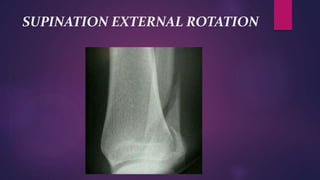

SUPINATION EXTERNAL ROTATION

INJURY

 This backward rotation of talus causes the lateral

malleolus to be pushed posteriorly rupturing the

Anterior tibio-fibular ligament .

 Low oblique fracture of the fibula passing downward

and forward to the level of ankle joint.

 At this stage if the deforming arrests- only injury is

undisplaced fibula fracture.